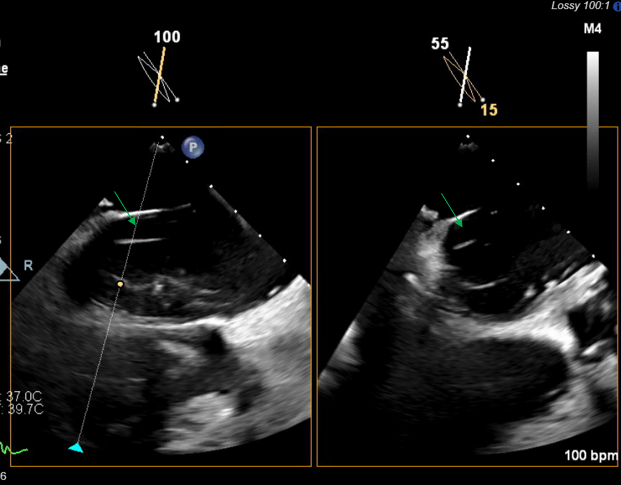

We present a 73-year-old female with history of rheumatic heart disease status post-mechanical mitral valve on warfarin, valvular atrial fibrillation, and alpha thalassemia who was admitted to an outside hospital with anterior ST-segment myocardial infarction. Coronary angiogram showed occluded left anterior descending artery (LAD) with acute thrombus status post-thrombectomy and balloon angioplasty. Her hospital course was complicated by subsequent ischemic cardiomyopathy with ejection fraction of 40% to 45%, pulmonary edema requiring positive pressure ventilation, and acute onset headaches. Computed tomography of her brain and chest showed bilateral mixed density subdural hematomas and a large left atrial appendage (LAA) thrombus (Figure 1). Warfarin was given for 1 day post-intervention, and then discontinued in the setting of brain bleeding. The patient was subsequently transferred to our center for consideration of neurosurgical intervention. No neurosurgical intervention was performed, as the patient’s brain bleeding remained stable and her sole neuro deficit was stable right-sided dysmetria.